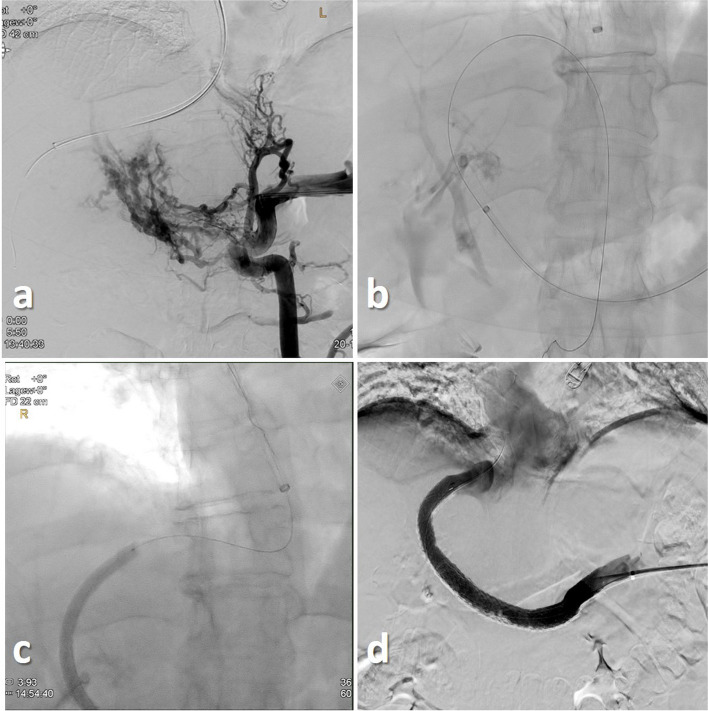

Background: Three patients with portal hypertension and gastrointestinal bleeding due to non-cirrhotic portal vein thrombosis were treated with portal venous recanalization transjugular intrahepatic portosystemic shunt (PVR-TIPS) via a trans-splenic access.

Main body: A "bottoms-up" retrograde puncture of the right hepatic vein was performed using a re-entry catheter to gain access to the right hepatic vein. In all patients a successful retrograde puncture of the right hepatic vein was achieved, thereby restoring the splenoportal tract.

Conclusion: Our cases present an alternative approach to treat chronic portal vein thrombosis expanding the possibilities of the PVR-TIPS procedure.